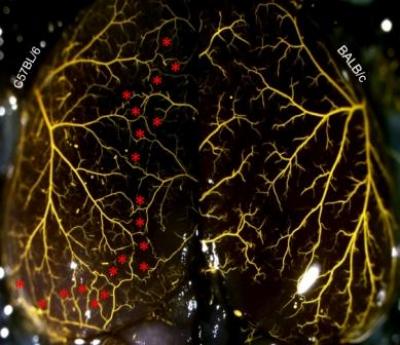

CHAPEL HILL – Researchers at the University of North Carolina at Chapel Hill School of Medicine have uncovered the genetic architecture controlling the growth of the collateral circulation – the "back-up" blood vessels that can provide oxygen to starved tissues in the event of a heart attack or stroke.

The UNC research, conducted in animal models, combined classical genetic mouse crosses with a new genomic technology called association mapping to identify the section of DNA involved, starting with the whole genome, narrowing it down to several hundreds of genes and finally landing on nine candidates on mouse chromosome 7.